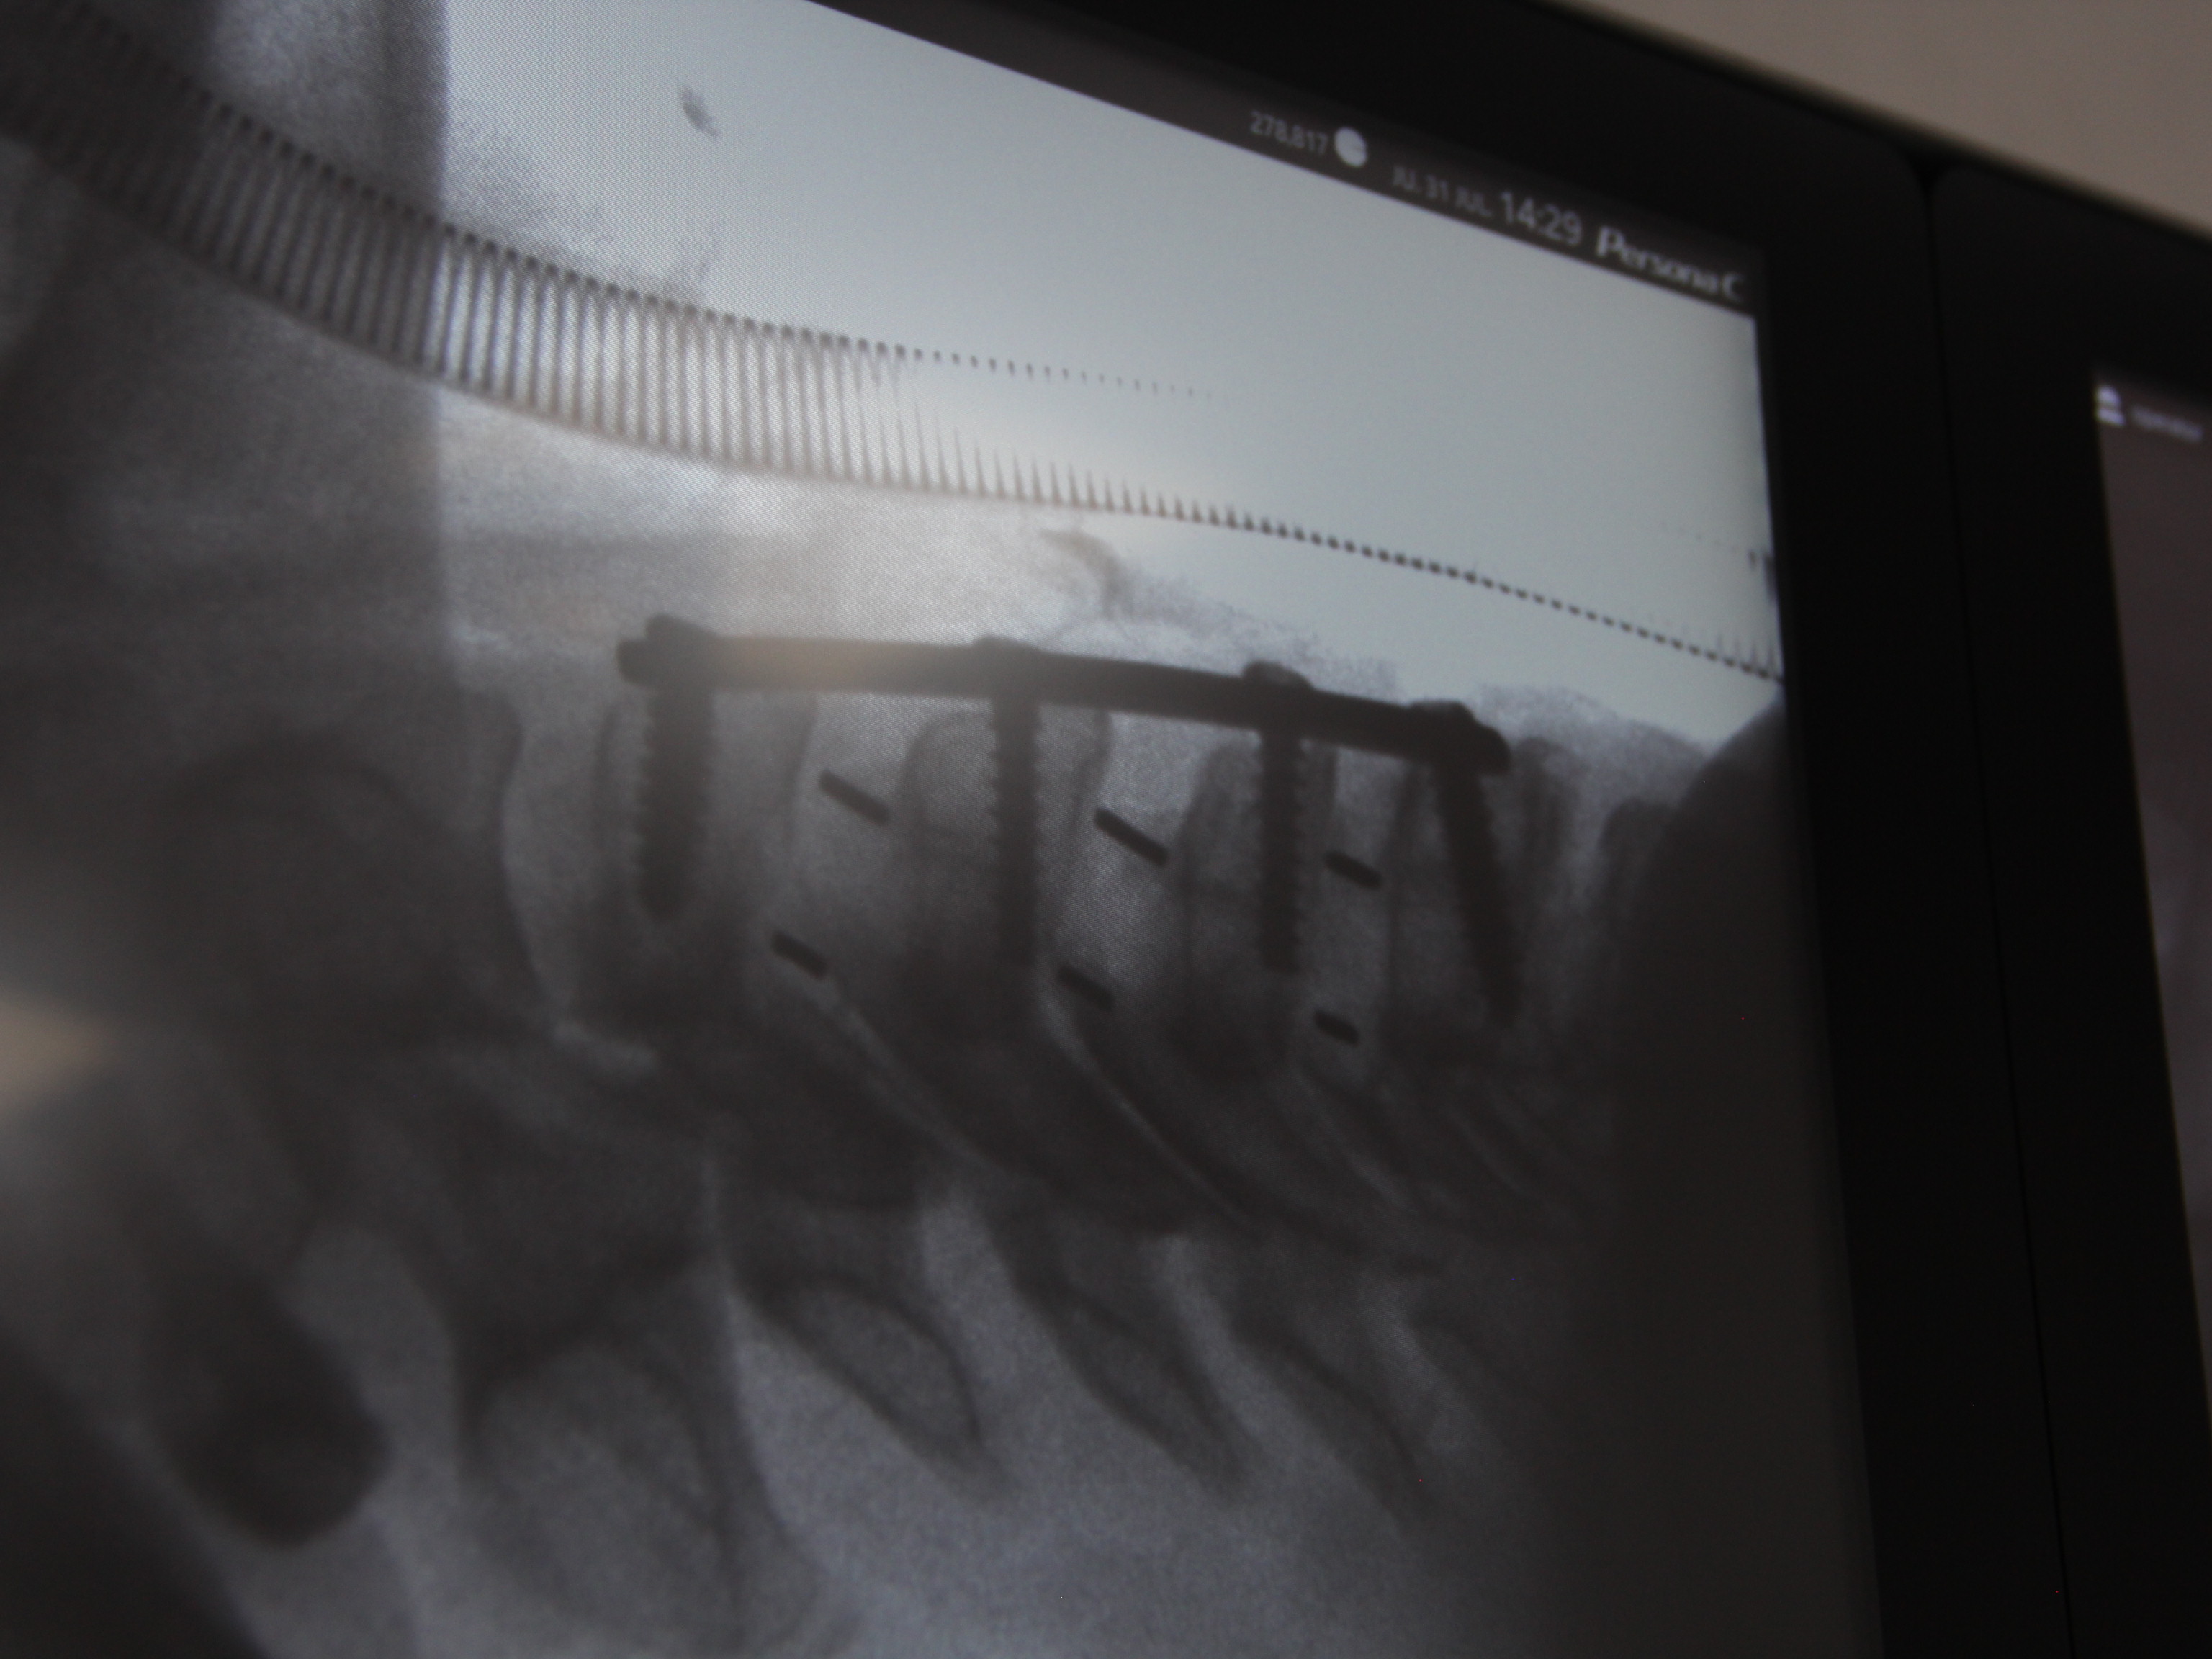

SURGERIES

RESULTS